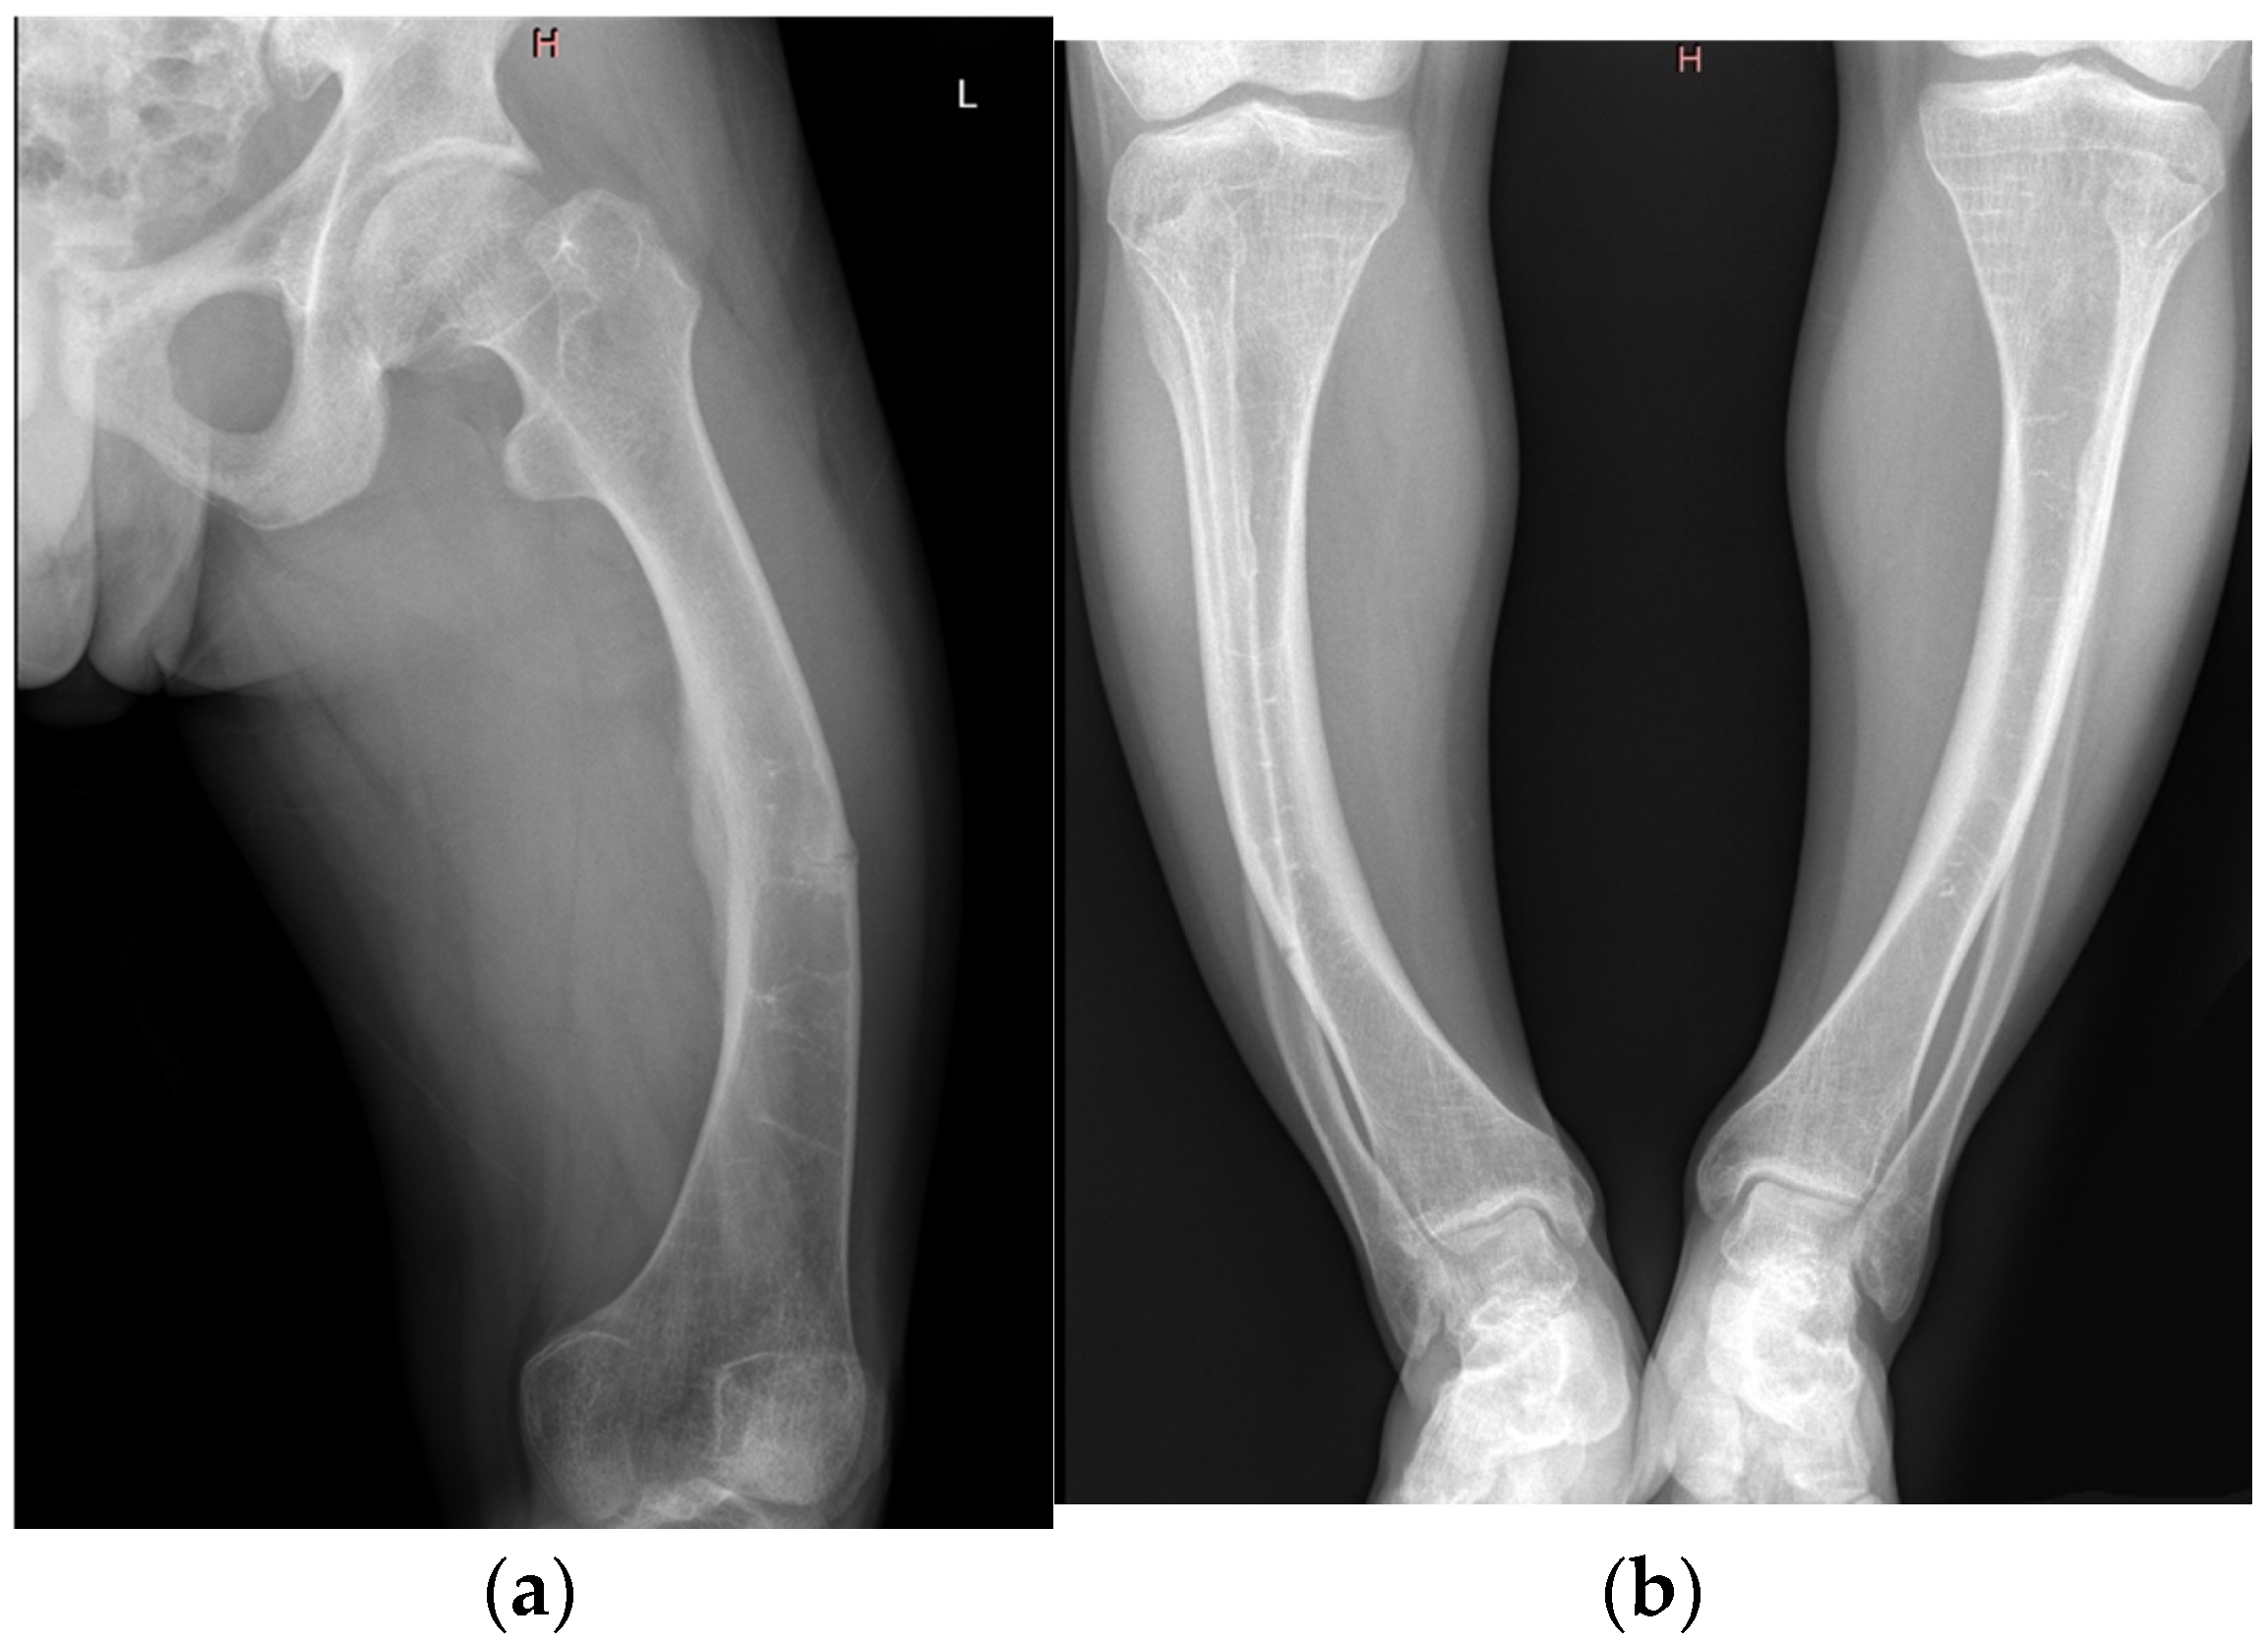

| Imaging findings | Radiography | Bilateral coxarthrosis and gonarthrosis, tibial osteosclerosis, no pseudofractures |

| Imaging findings | Radiography | Bowing of femurs and tibiae, pseudofracture in mid-femur |